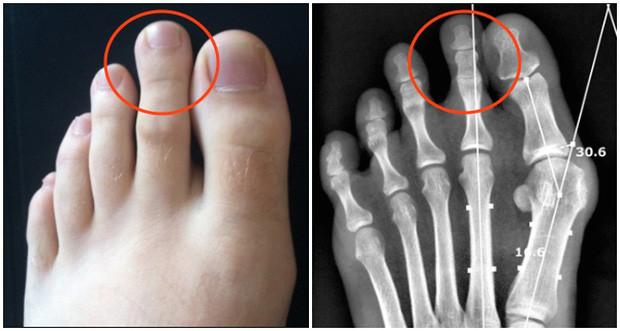

Khoảng cách lớn giữa ngón thứ hai và thứ ba. Chủ nhân của kiểu bàn chân này là người có thể tách bạch cảm xúc với lý trí. Nếu có kiểu bàn chân như vậy, bạn có thể cân nhắc trở thành một nhà ngoại giao, nhà phân tích hoặc thương nhân. * Thông tin trên chỉ mang tính chiêm nghiệm, tham khảo.